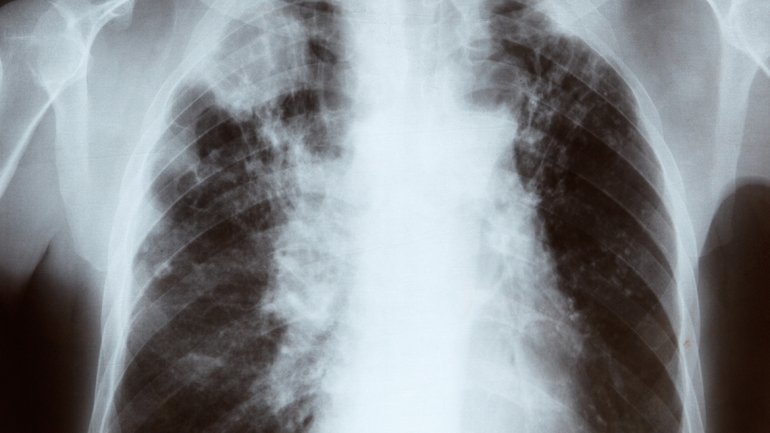

Así lo definió el médico oncólogo Alejandro Turek, en un informe publicado hoy. Adelantándose a la Semana libre de humo (24 al 31 de mayo), Turek destacó que “se sospecha de la relación tabaco – cáncer en otros diagnósticos oncológicos”, y sentenció: “el tabaquismo en todas sus formas es cancerígeno».

«Al fumar tomamos la chance de tener cáncer de labio, boca, lengua, paladar, faringe, órganos de la cabeza y el cuello, laringe, tráquea, bronquios, pulmón, algunos del aparato digestivo como el esófago y páncreas, riñón, vejiga y hasta algunos tumores que parecen no estar relacionados a este consumo aumentan su incidencia en fumadores como el cérvix uterino y la leucemia aguda”, especificó el profesional.